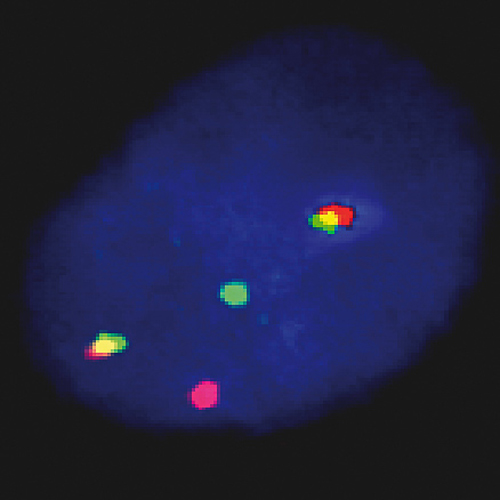

FGFR3 / IGH t(4;14) Fusion probe hybridized to MM patient material showing t(4;14) translocation (2RG1R1G). Image kindly provided by Prof. Jauch, Heidelberg.

The t(4;14) translocation is undetectable by conventional cytogenetics. The breakpoints on chromosome 4 occur within an approximately 113-kb region located in small part of a conserved gene cluster including the transforming acidic coiled-coil protein 3 (TACC3), fibroblast growth factor receptor 3 (FGFR3), and multiple myeloma SET domain-containing protein (MMSET). The translocation is indicative of poor survival and poor response to chemotherapy. The FGFR3 / IGH t(4;14)(p16;q32) Fusion specific FISH probe is optimized to detect the reciprocal translocation t(4;14) in a dual-color, dual-fusion assay.